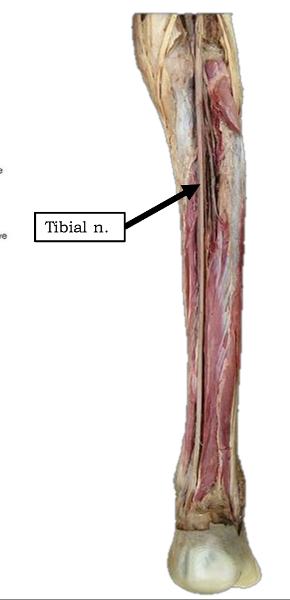

What is the pathway of the tibial nerve?

runs through popliteal fossa

runs with tom dick AN harry though medial malleoulus

bifurcates into medial and lateral plantar nerves

origin and distribution of tibial nerve

O sciatic nerve

C forms as sciatic nerve bifurcates at apex of popliteal fossa; descends through popliteal fossa; runs inferior to tibialis posterior with posterior tibial vessels; terminates beneath flexor retinaculum by dividing into medial and lateral plantar nerves

D supplies plantar flexor muscles of the posterior compartment of the leg and knee joint